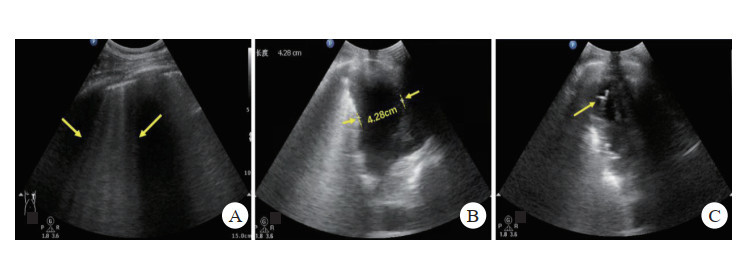

⑵后送载体平台救治,航天救护中所用后送载体主要为直升机和地面医监医救车,直升机是航天医疗救护的首选载体。如遇特殊地形或极端天气,直升机不能起飞或无法降落,医监医救车可第一时间进入现场展开救治运送。直升机作为重要的战场急救医疗救护的载体之一,转送速度快,受地形影响小,在野战医疗急救中发挥了重要作用,直升机医疗急救体系(helicopter emergency medical services, HEMS)在降低创伤患者病死率方面与地面医疗急救体系(ground emergency medical services, GEMS)疗效一致,但比地面救治转运距离更远[13],从而为伤情的急救及后送赢得了宝贵的时间,已成为空间站任务院前急救中的主体。但直升机内强大的噪声,不利于临床医生进行常规心肺听诊等物理检查,因此近几年提出了直升机重点超声检查(point-of-care ultrasound, PoCUS)概念[14],即以直升机作为急救平台,在直升机上进行快速且有针对性的超声探查,研究显示在直升机上所获得的超声影像的质量并不劣于地面救治[15]。故在后送载体内运用FAST或E-FAST的快速筛查法,可行性强,是快速发现如钝性腹部创伤、血气胸等一些引起的血流动力学不稳定的隐匿伤情的可靠方法[16],为院前救治(图 1)赢得宝贵时间。

|

| 图 1 航天员返回舱着陆后院前救治体系流程 |

|

|